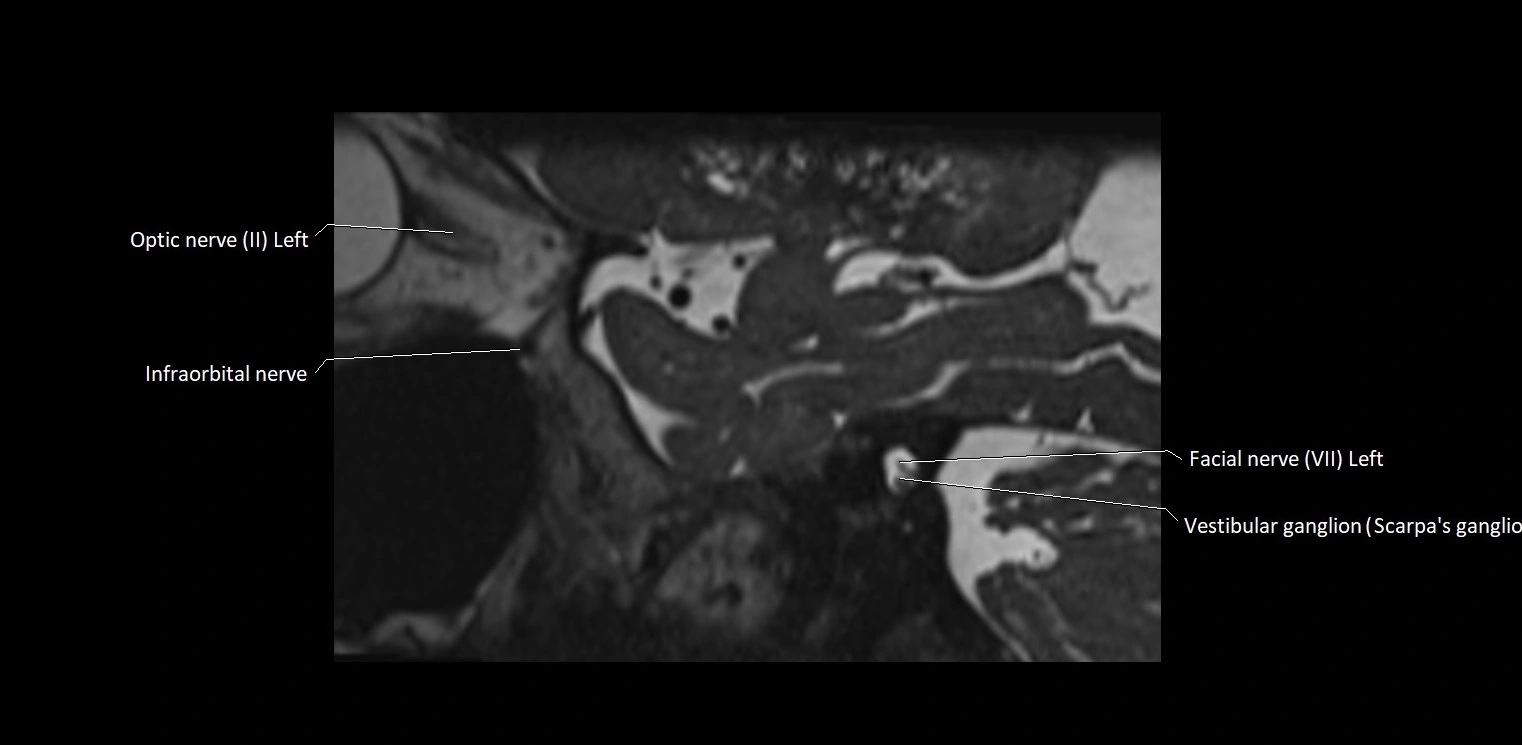

MRI Appearance

• The abducens nerve is a small, thin, linear structure

• Best visualized on high-resolution T2-weighted 3D MRI sequences (e.g., FIESTA or CISS)

• Seen as a hypointense (dark) line running from the brainstem at the pontomedullary junction, traversing the prepontine cistern, and entering Dorello’s canal under the petrosphenoidal ligament, then into the cavernous sinus, and finally the orbit

• May be challenging to visualize in standard MRI due to its small size

• Pathology may be inferred by absence, displacement, or enhancement of the nerve

MRI images

image